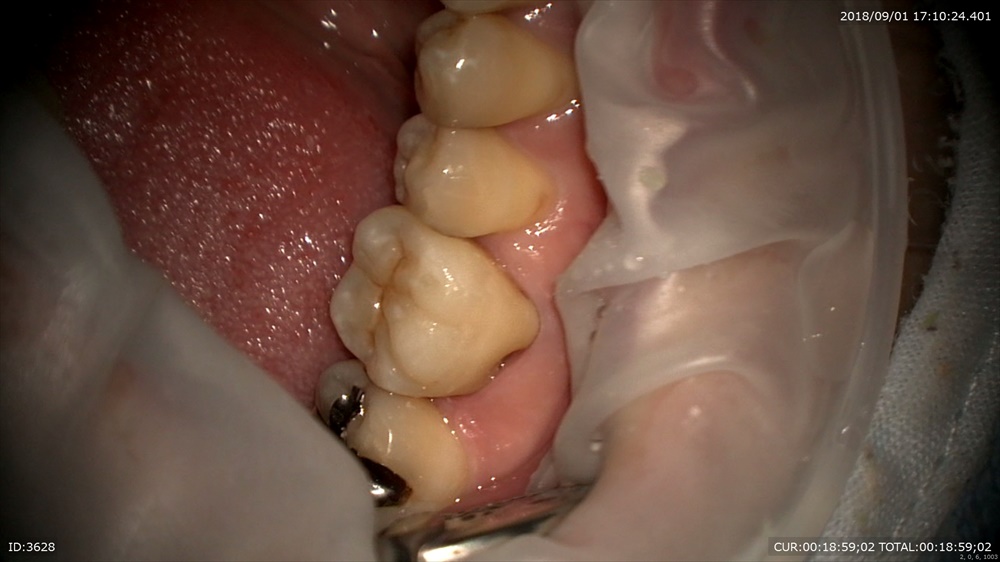

歯周病治療後型取りをして

本日セット 技工士間中先生

少しの段差もありません、

このように重症の虫歯でも抜歯せずに治療ができます。ただし、